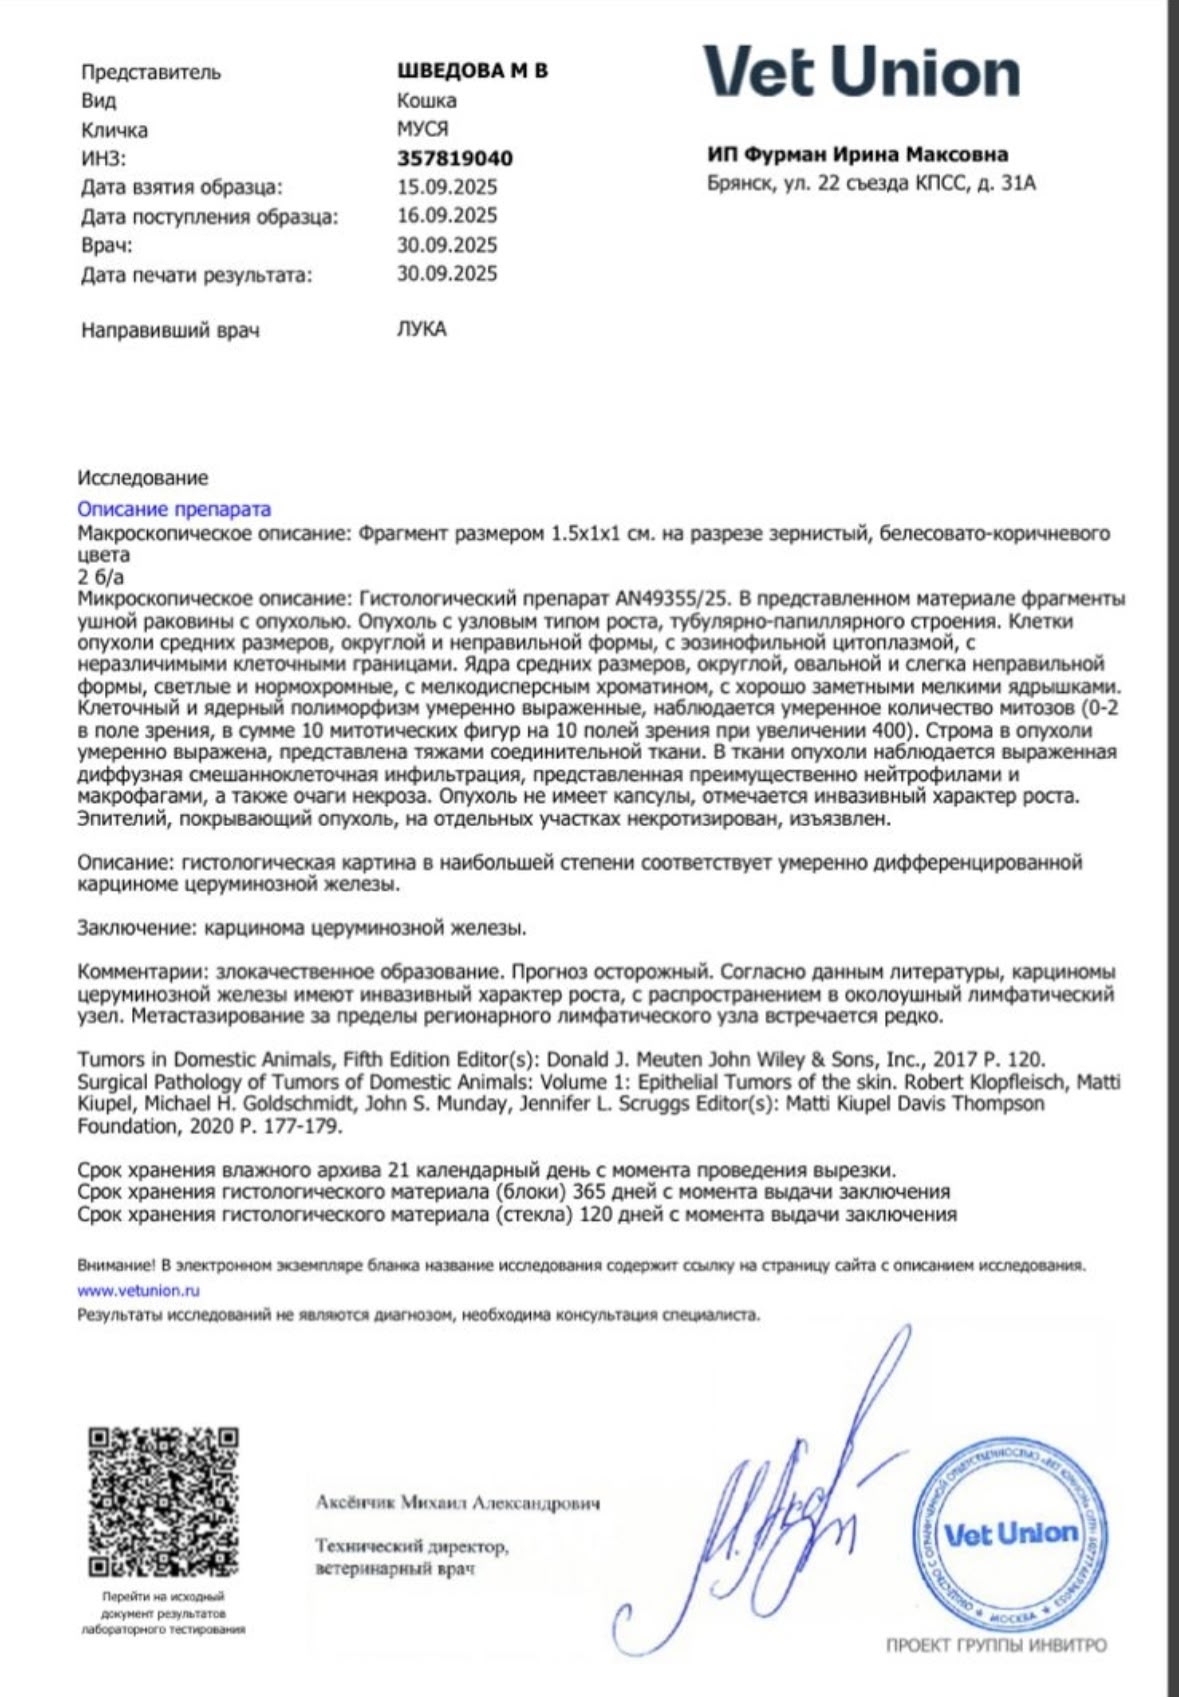

Она сама пришла к нам за помощью, по результатам анализов, карцинома😱Удалили слуховой проход, ушко оставили и зашили, стерилизовали, вылечили от лишая, по рентгену пуля в носу, но и это ещё не всё, диабет, сахар 19, 21😱 Сейчас Мусенька на передержке с медуходом на 1 месяц, для подбора дозировки инсулина и стабилизации сахара 💔Поэтому просим всех неравнодушных о помощи 🙏❤